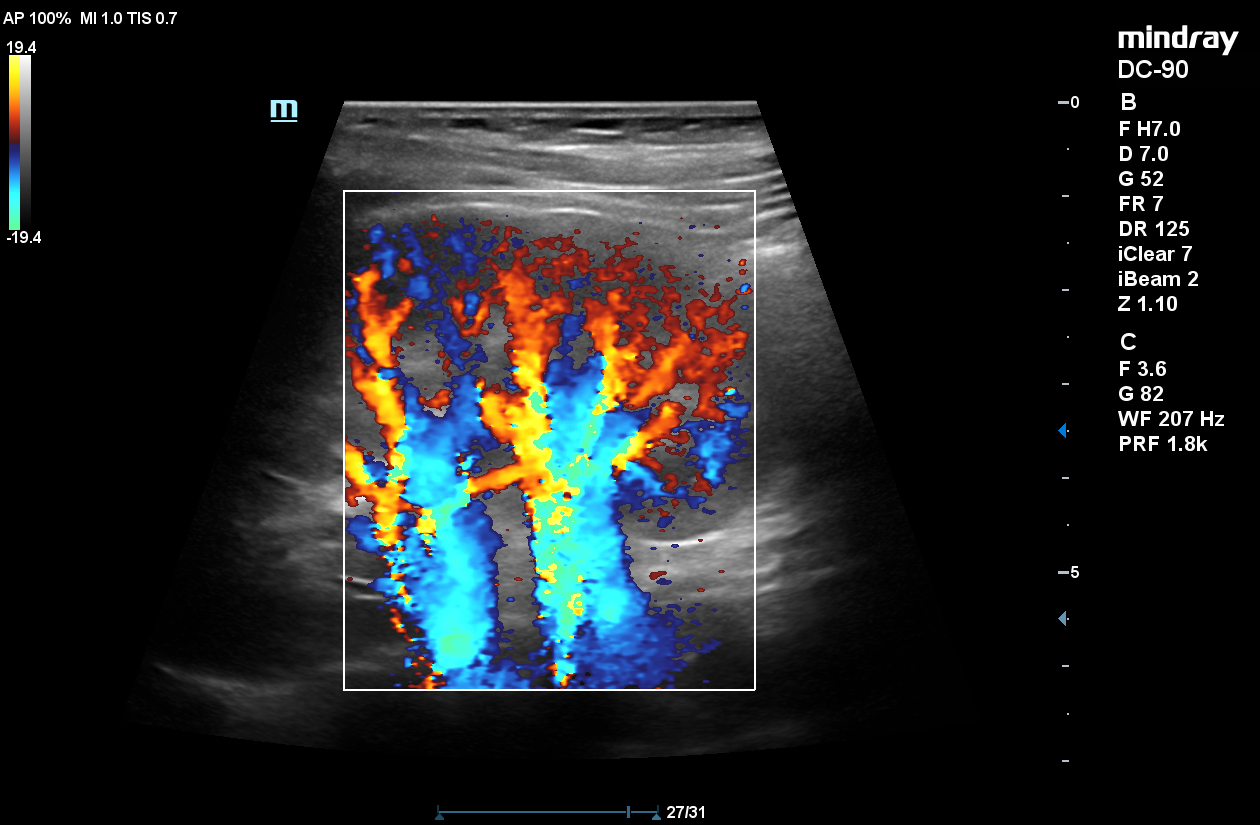

UWN+ CEUS

Mindray’s second generation Ultra-Wideband Non-Linear (UWN+) contrast enhanced ultrasound (CEUS) imaging uses both harmonic and fundamental signals to improve contrast and temporal resolution during CEUS studies. X-insight, the technology that powers the DC-90, allows for a longer duration of perfusion in the tissues.